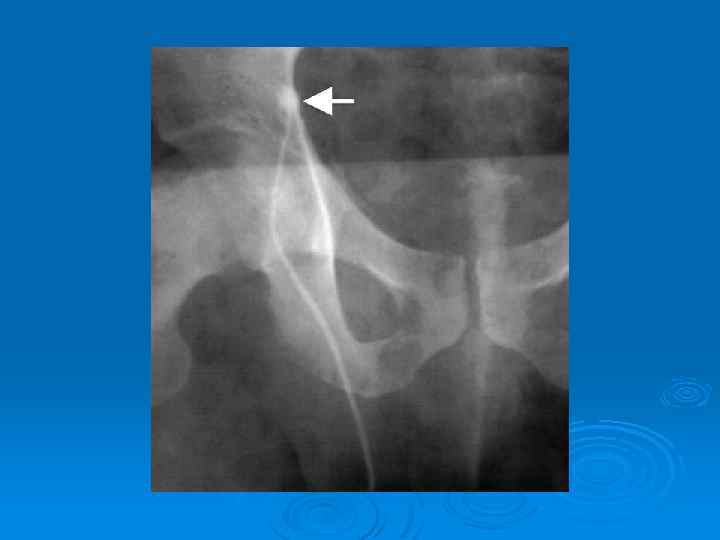

Флебография

варикоцеле